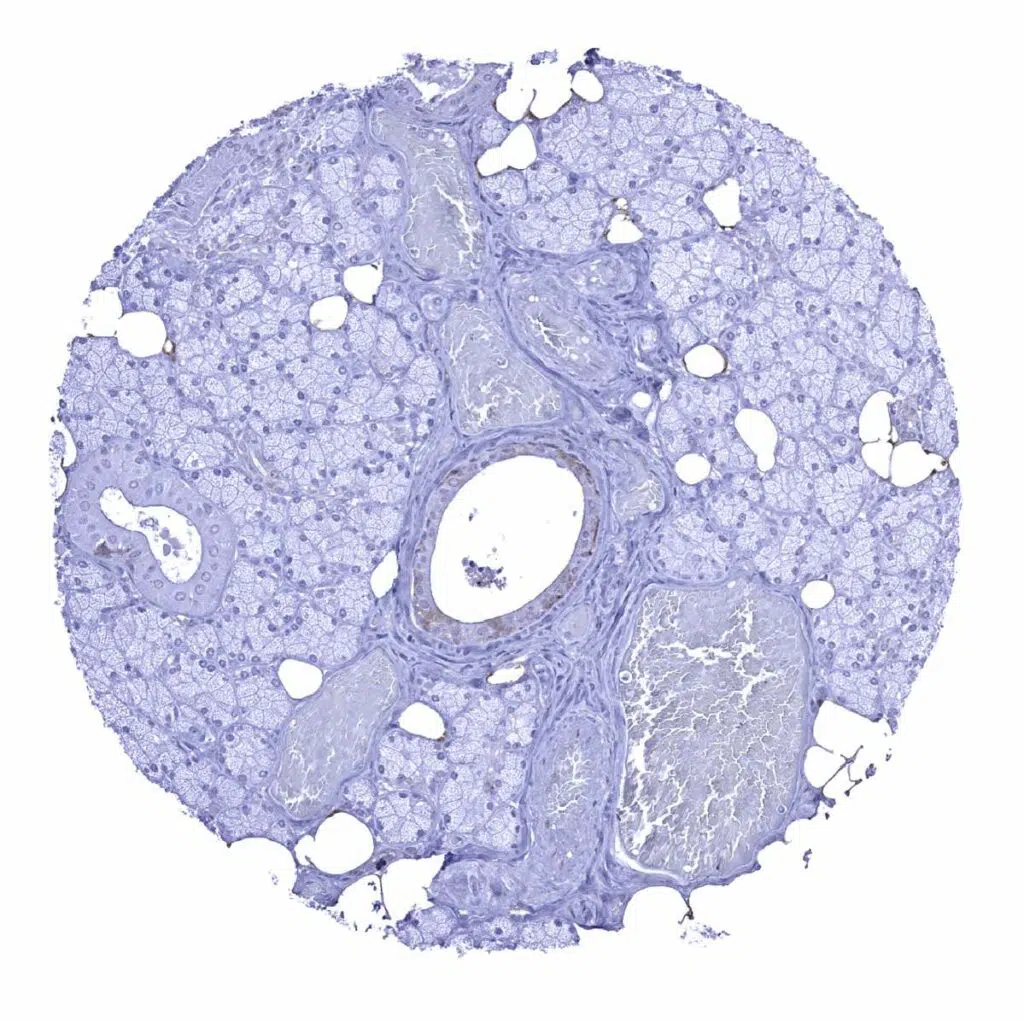

Liver – GS staining is strong in centrilobular hepatocytes, weak to moderate in Kupffer cells but absent in periportal hepatocytes

Liver – GS staining is weak in Kupffer cells but absent in periportal hepatocytes and bile ducts

Liver – A weak GS staining is seen in Kupffer cells